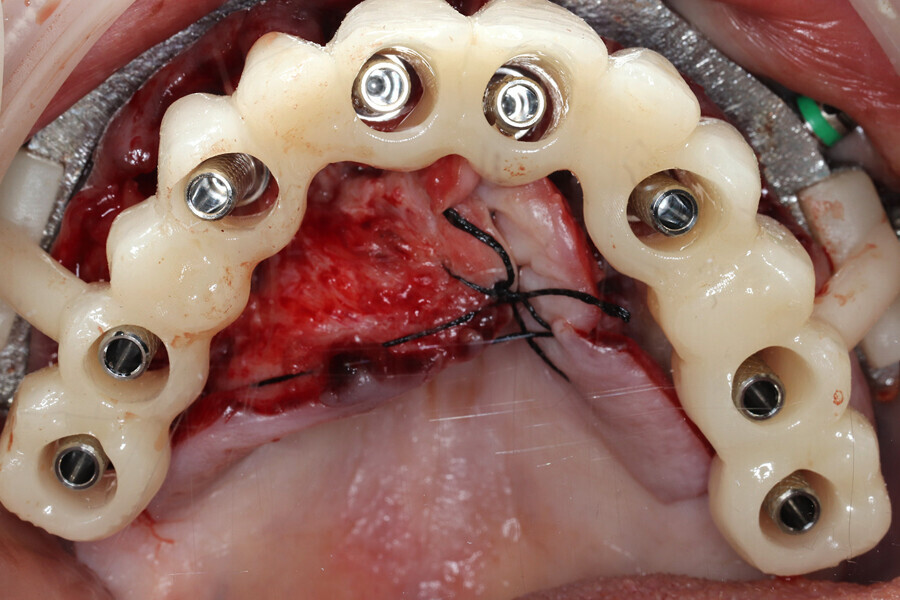

A biologically driven drilling system for anatomical alveolar sculpting (Universal Shapers) was employed (Fig. 13). The alveolar bone was scalloped utilising the diamond shaper drills for both implant and pontic sites to promote emergence profiles for enhanced aesthetics according to the basic tooth size requirements assessed from the initial data collection. The surgery was uneventful except for a mild complication during the extraction of the impacted mandibular canine. Implant stability was measured with resonance frequency analysis (implant stability quotient) to validate loading. MUAs were secured to each implant based on the rotational positions predetermined by the surgical planning. Deficient sites and residual tooth sockets were then grafted with the ground dentine autograft, covered with platelet-rich fibrin membranes and sutured around the healing abutments. Provisional restorations were fabricated using the C2F protocol (Figs. 14a & b).4 After customisation and polishing, the provisional restorations were inserted and allowed to heal (Fig. 14c–e).

During the subsequent postoperative visits, the patient described being extremely happy with his newly rehabilitated mouth. As the preliminary provisional restorations had been designed based on the desired virtual result, it was possible to make changes as necessary for the final restorations. A slight discrepancy was observed in initial tooth size and midline position, and this was noted in order to be corrected during finalisation of the monolithic zirconia restorations. The patient tolerated the 2 mm increase in VDO, and minimal adjustments to the occlusion were accomplished through digital articulation (OccluSense, Bausch). Tissue healing was unremarkable apart from minor loss in alveolar height and soft tissue in the impacted canine extraction site.

The data collected was sent through a scanning software portal (Medit Scan for Clinics) to the dental laboratory with requested changes for correction of the desired smile design. Utilising advanced planning features in the design software (exocad), the midline and tooth size changes were corrected. 3D-printed maxillary and mandibular PMMA restorations were used for try-in using the direct-to-MUA screws (Vortex LA VIS; Fig. 16a). Fit, phonetics, aesthetics and occlusion were evaluated and confirmed using digital articulation (OccluSense; Fig. 16b). The patient was extremely satisfied with the printed try-ins. Since no adjustments were required, the patient was allowed to leave with the printed try-ins as new provisional restorations made from extra-strong resin. The new provisional restorations were worn for ten days to confirm form and function. The final shade was chosen, and metal-free monolithic zirconia restorations were then fabricated by the laboratory.

The final restorations were passively and accurately seated ten days later uneventfully using Vortex LA VIS screws. Confirmation records were taken with photographs, radiographs and digital articulation to recheck fit, function, phonetics and occlusion (Fig. 17a). The patient was extremely satisfied with his final restorations, describing the process as life-changing and surprisingly fast in comparison with what he had heard about full-mouth implant therapy. He was especially pleased with the speed at which the final process was able to be completed (Figs. 17b & c).